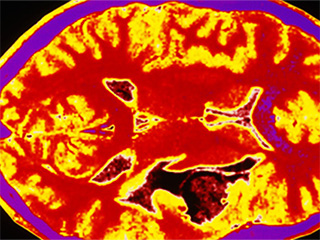

कैंसर (Cancer In Hindi) मनुष्यों तक ही सीमित नहीं है बल्कि जानवरों और अन्य जीवों को भी कैंसर हो सकता है। कैंसर दुनिया में दूसरा सबसे अधिक जानलेवा रोग है, और इंसानों की मौतों का सबसे आम कारण भी है। यह तब शुरू होता है जब एक कोशिका अपना स्‍वरूप बदलती है और तेजी से बढ़ने और विभाजित होने लगती है। पहले एक कोशिका दो कोशिकाओं में विभाजित होती हैं, फिर चार, आठ और इसी तरह जब तक वे कोशिकाओं का अधिक संख्‍या में निर्माण नहीं करती हैं, जिन्हें ट्यूमर कहा जाता है। हालांकि, हर ट्यूमर कैंसर नहीं होता है। जब यह अनियंत्रित रूप से बढ़ता है तो यह अक्सर पूरे शरीर में फैलने की क्षमता रखता है।

कैंसर, शरीर में कहीं भी असामान्य कोशिकाओं की अनियंत्रित वृद्धि है। स्तन कैंसर, त्वचा कैंसर, फेफड़ों का कैंसर, पेट का कैंसर, प्रोस्टेट कैंसर और लिंफोमा सहित 100 से अधिक प्रकार के कैंसर हैं। लक्षण प्रकार के आधार पर भिन्न होते हैं। इन असामान्य कोशिकाओं को कैंसर कोशिका, मैलिग्नैंट ट्यूमर या ट्यूमर कोशिकाएं कहा जाता है। ये कोशिकाएं शरीर के सामान्य ऊतकों में घुसपैठ कर सकती हैं। कई कैंसर और असामान्य कोशिकाएं जो कैंसर के ऊतकों (Tissues) की रचना करती हैं, उन्हें उस ऊतक के नाम से पहचाना जाता है, जो असामान्य कोशिकाओं से उत्पन्न हुआ है (उदाहरण के लिए, स्तन कैंसर, फेफड़े का कैंसर, कोलोरेक्टल कैंसर)। कैंसर उपचार में कीमोथेरेपी, विकिरण (Radiation) और सर्जरी शामिल हैं।